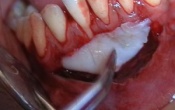

La greffe gingivale libre

12/11/2009 | Commentaires (

2

)